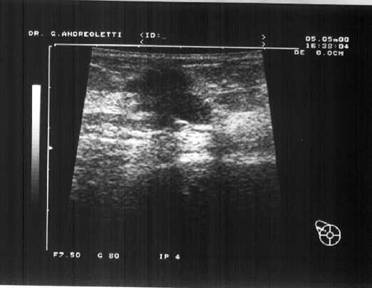

Aspect ecografic

In faza acuta regasim semnele obisnuite ale inflamatiei:

- ingrosare cutanata

- disparitia grasimii subcutanate

- hiperecogenitate globala

Ectaziile canalare pot fi puse in evidenta sub forma unor structuri hipoecogene cu contururi neregulate, tubulare orientate spre mamelon.

In stadiul de colectie exista o imagine rotunjita, ovoida cu ecouri intense neomogene, cu diverse marimi si repartitii

Contururile sunt mai mult sau mai putin neregulate si accentuarea posterioara moderata, variabila, urmarind continutul mai mult sau mai putin extins. Nu exista atenuare posterioara pentru ca peretii sunt ingrosati. Pot aparea cateva cloazonari interne precum si imagini de nivele lichidiene in caz de sedimentare a puroiului. Acest examen idispensabil este primul si deseori singurul facut tinerei fete. Este neiradiant, putin dureros, deseori suficient pentru diagnostic, util in realizarea prelevarilor si a supravegherii.